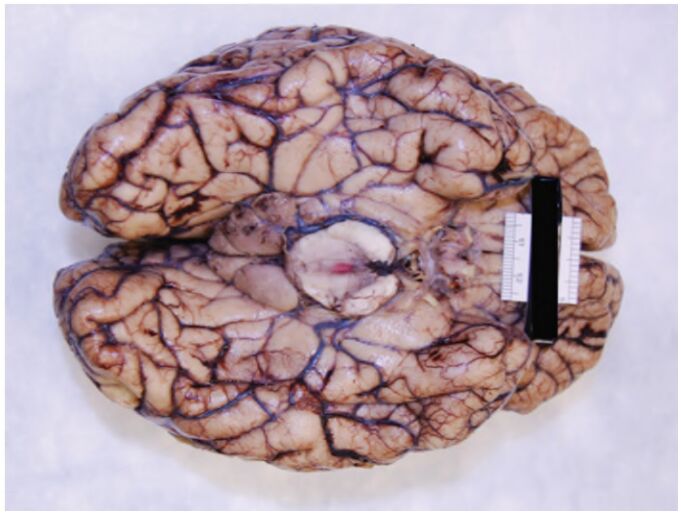

36 下圖是一張解剖後大腦以福馬林固後的照片,肉眼觀察下的病理診斷最恰當為何? (A)細菌性腦膜炎 (B)水腦症 (C)顳葉腦疝(Uncal herniation) (D)腦膜瘤(Meningioma)